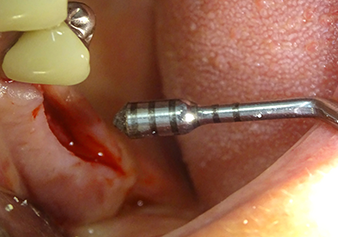

Preparazione e accrescimento della sede dell'impianto

Dopo un controllo intermedio (Fig. 4) è stata eseguita un'ulteriore fase di preparazione (Fig. 5). Lo strumento idraulico Z35P è stato utilizzato in un secondo momento per sollevare la membrana sino alla posizione desiderata (Fig. 6 e 7). In seguito alla suddetta operazione, si è proceduto ad una ulteriore preparazione piezochirurgica della sede dell'impianto conclusasi con l'applicazione della fresa e della fresa a spallamento sul diametro dell'impianto di 4,8 mm. Il materiale di rinforzo (dimensione delle particelle di ca. 0,8 - 1,6 mm) è stato introdotto sotto la membrana di Schneider prima che venisse inserito l'impianto (Fig. 8).